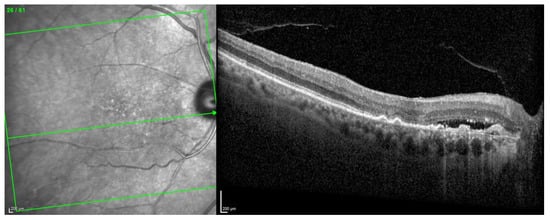

The OCT scan demonstrated a type 1 MNV with PED and BALAD in the right eye. The ceiling of the BALAD presented hyper-reflective foci. The EZ zone was attenuated at the floor (Figure 12).

Figure 12.

Case 7. Heidelberg Spectralis optical coherence tomography shows a peripapillary type 1 MNV with subretinal fluid and BALAD in the right eye.

The OCTA scan confirmed the presence of the right peripapillary MNV (Figure 13).

Figure 13.

Case 7. Heidelberg Spectralis optical coherence tomography angiography shows a peripapillary subretinal neovascular membrane in the right eye.

These features were shown to be partially responsive to the treatment. The BVCA was stable over the treatment period.